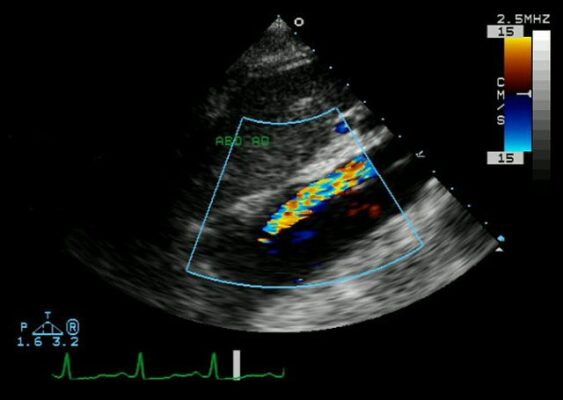

- Aort diseksiyonunun ekokardiyogramı

Aort diseksiyonu, belirtileri birçok başka hastalıkla (özellikle kalp krizi) karışabildiği için “büyük taklitçi” olarak da bilinir. Tanı süreci, hekimin hastanın anlattığı tipik öyküden (ani, yırtılır tarzda ağrı) ve muayene bulgularından (iki kol arası tansiyon farkı gibi) şüphelenmesiyle başlar.

Transözofageal Ekokardiyografi (TÖE) ise, özellikle durumu çok kritik olan ve tomografiye taşınamayan hastalar için paha biçilmezdir. Ucunda küçük bir ultrason probu olan esnek bir tüp, ağız yoluyla yemek borusuna indirilir. Yemek borusu, kalbe ve aorta çok yakın olduğu için, bu yöntemle aortun ve kalbin çok net, gerçek zamanlı görüntüleri elde edilir. Radyasyon içermemesi ve yatak başında yapılabilmesi en büyük avantajlarıdır.